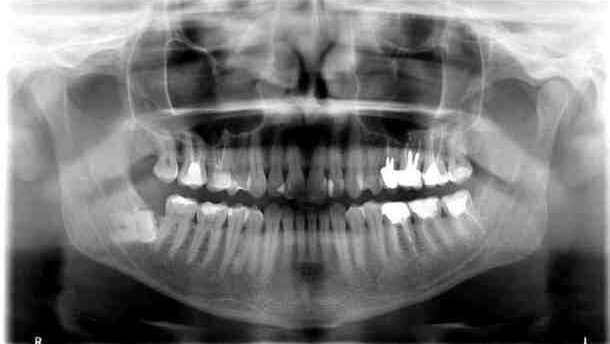

W badaniu fizykalnym stwierdzono tkliwość palpacyjną okolicy 48, niewielkie zapalenie otaczającej błony śluzowej oraz niewielką, jednak wyczuwalną ruchomość patologiczną w okolicy kąta po stronie prawej, z nasilaniem się bólu w trakcie badania ruchomości, ponadto dodatni objaw Vincenta po stronie prawej. Wykonane zdjęcie rtg pantomograficzne wykazało szczelinę złamania w okolicy 48, najprawdopodobniej powstałą podczas usuwania zęba zatrzymanego. Jest również prawdopodobne, iż korzystny przebieg linii złamania i niejako „zakleszczenie” odłamów oraz brak wyczuwalnego klinicznie ich przemieszczenia w postaci prawidłowego zgryzu zmniejszyły ryzyko rozwinięcia się ostrego zakażenia miejscowego (Ryc. 2).

Pacjent, lat 27, także zgłosił się do tutejszej poradni chirurgii stomatologicznej celem kontroli stanu miejscowego po przeprowadzonej 3 miesiące wcześniej ekstrakcji zęba 16. Powtarzające się okresowe dolegliwości bólowe oraz konieczność przyjmowania leków przeciwbólowych skłoniły pacjenta do szukania pomocy specjalistycznej. Pacjent poddała się badaniu rtg pantomograficzne we własnym zakresie. Wykazało ono, iż w okolicy 16 pozostawiono fragment korzenia podniebiennego i zmianę okołowierzchołkową o charakterze torbieli korzeniowej. Ponadto, pomiędzy fragmentem korzenia podniebiennego zęba 16 a wierzchołkiem korzenia zęba 15 stwierdzono ciało obce o przybliżonych wymiarach 8:3 mm i wysyceniu sugerującym obecność metalu. W badaniu klinicznym okolica 16 nie wykazywała zmian zapalnych, rana poekstrakcyjna była prawidłowo wygojona.